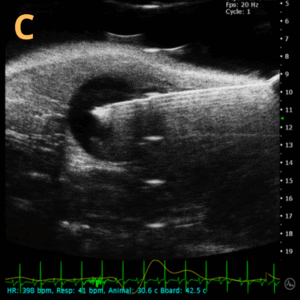

Ultrasound-guided Injections C